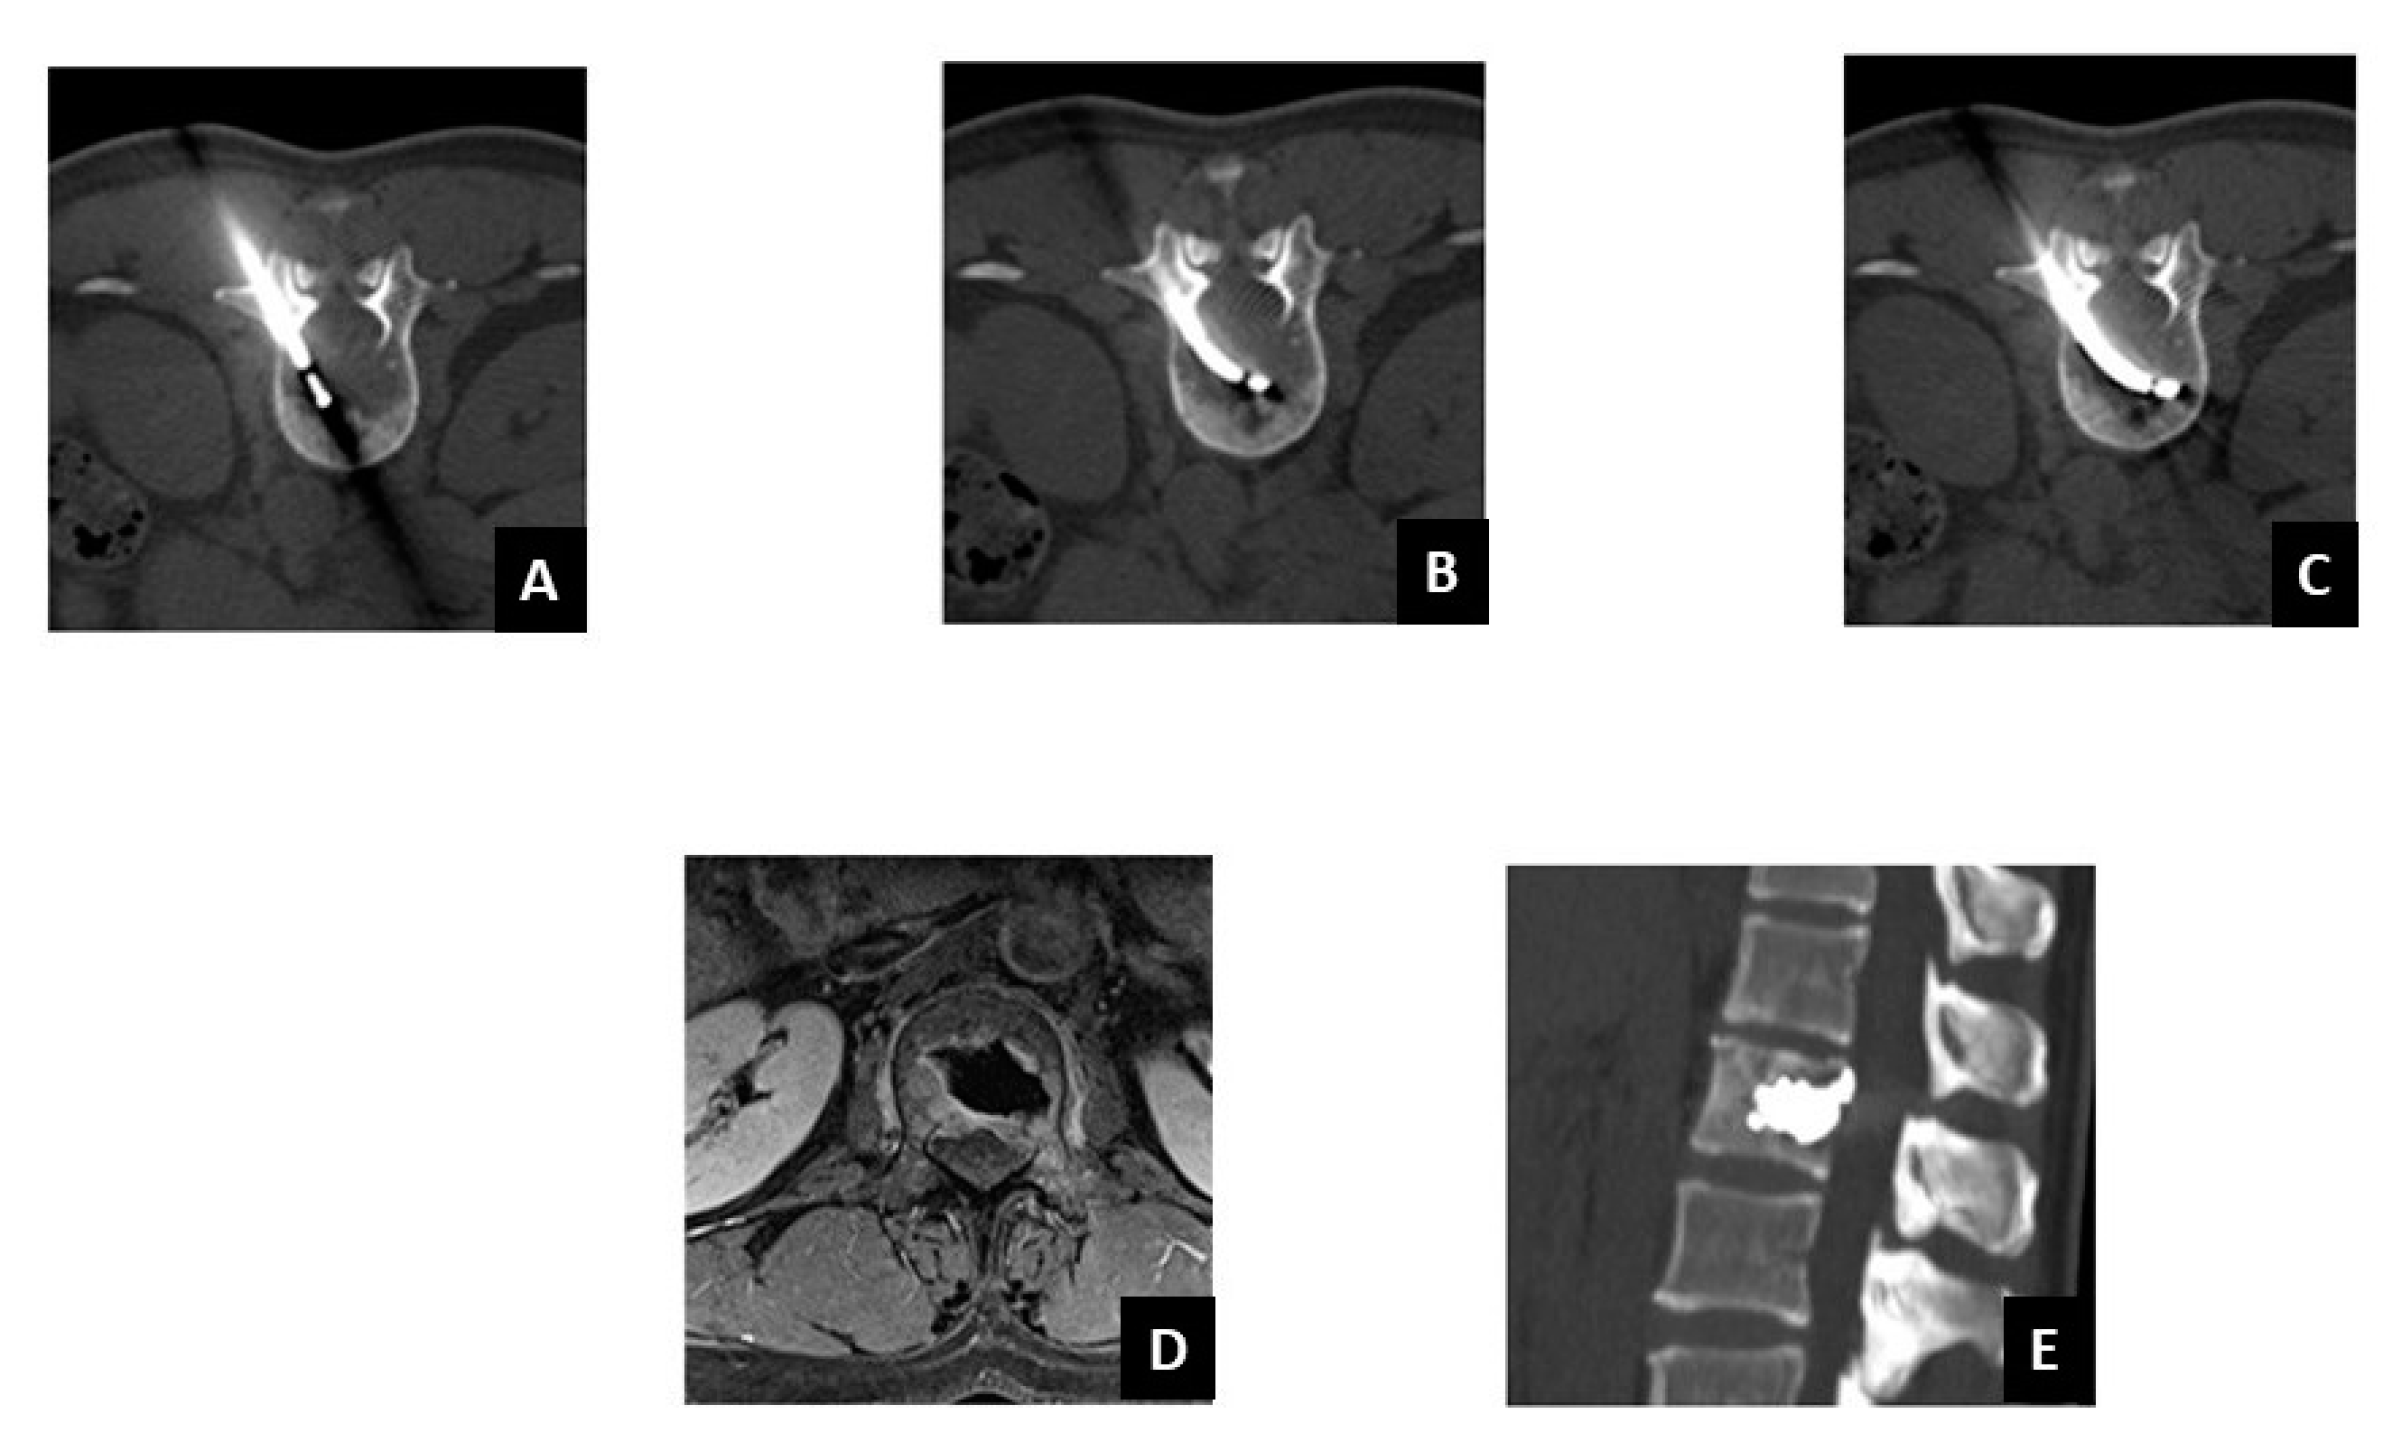

2.3. Target Radiofrequency Ablation (tRFA) and Vertebral Augmentation (VA) Procedure